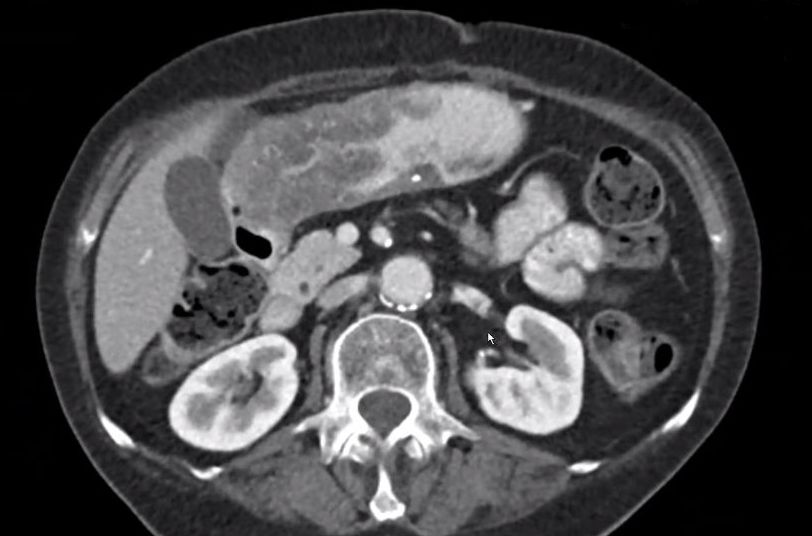

| Magenantrum | 54-jährige Frau mit obstruierendem Magenantrumkarzinom. ![]() |